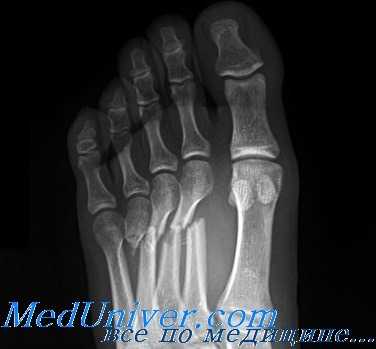

Переломы костей плюсны

Переломы костей плюсны возникают при ударе, падении тяжелого предмета или сдавлении стопы. Сопровождаются болями и нарастающим отеком в переднем отделе стопы. Точное определение места повреждения без рентгенографии затруднено, поскольку боль носит разлитой характер. Рентгенография стопы обычно помогает получить всю необходимую информацию касательно уровня и характера перелома. МРТ и КТ стопы требуются крайне редко.

Переломы плюсневых костей

Переломы плюсневых костей по частоте занимают первое место среди всех переломов костей стопы. Обычно возникают при прямом воздействии травмирующей силы (сдавление стопы, падение тяжести или переезд стопы колесом). Могут быть множественными или одиночными. В зависимости от уровня повреждения выделяют переломы головки, шейки и тела плюсневых костей.

Одиночные переломы плюсневых костей очень редко сопровождаются значительным смещение фрагментов, поскольку оставшиеся целыми кости плюсны выполняют функцию естественной шины, удерживая отломки от смещения.

При одиночных переломах плюсневых костей выявляется локальный отек на тыле и подошве, боль при опоре и прощупывании. Множественные переломы плюсневых костей сопровождаются выраженным отеком всей стопы, кровоизлияниями, болью при пальпации. Опора затруднена или невозможна из-за боли. Возможна деформация стопы. Диагноз подтверждается данными рентгенографии в 2-х проекциях, а при переломах основания костей плюсны – в 3-х проекциях.